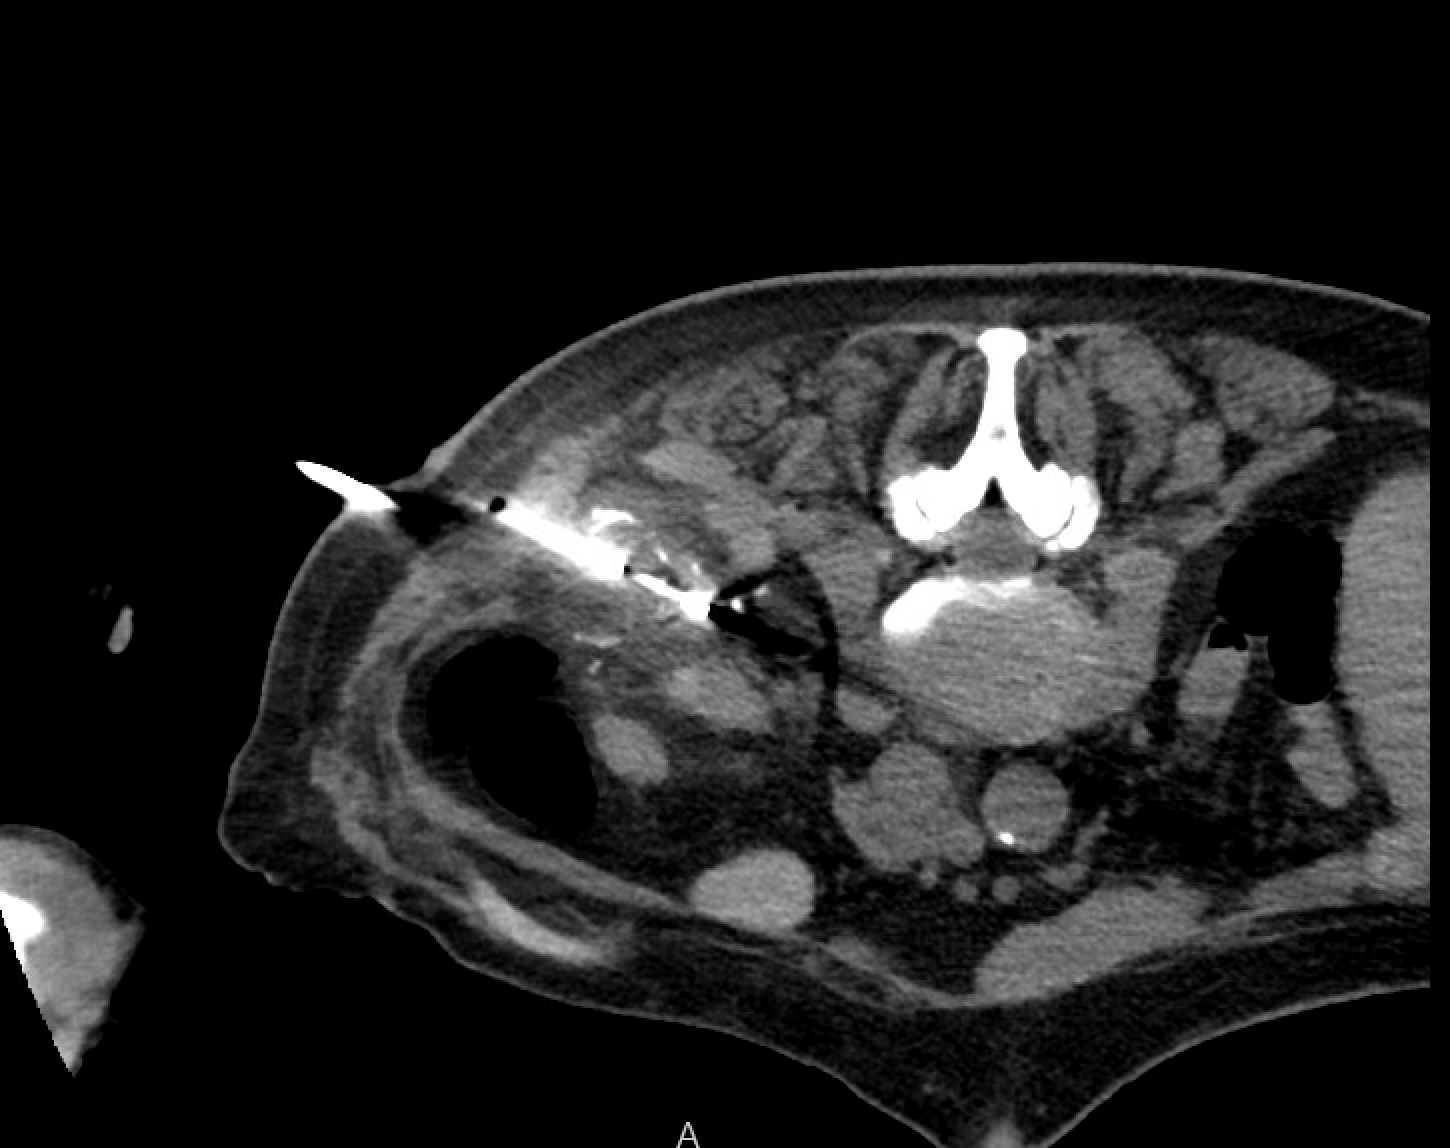

Pre-cryoablation renal mass with lipiodol tumor staining to define margins for probe placement.Pre-ablation angiogram demonstrating lipiodol tumor staining — selective injection used to mark tumor vascularity and guide probe targeting.

CT during cryoablation showing ice ball encompassing the renal mass — the hypodense ice ball should extend 5–10 mm beyond the tumor edge to achieve adequate lethal margin.